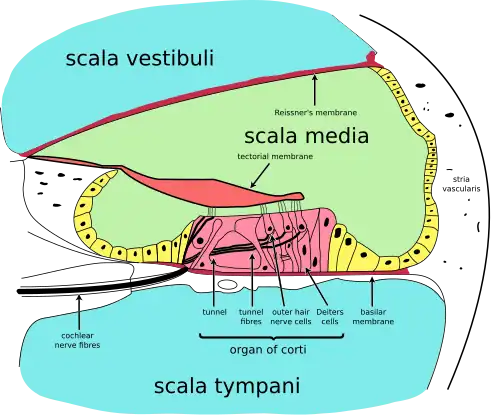

It is filled with two different fluids separated in three different channels that run together from the base of the stapes to the apex of the cochlea, however two of the channels are separated by Raleigh's membrane, which is thin and flexible enough to be neglected from a hydromechanical point of view.[8] The vibrations are transmitted directly from the base-plate of the stapes, the last of the three ossicles, to the contained fluid. The cochlea is divided down the middle by the basilar membrane which is a partly bony and partly gelatinous membrane. It is on this membrane that the organ of corti and the infamous hair cells reside.

The three Fluid filled cavities

The three Fluid filled cavities

The basilar membrane

As previously mentioned, the basilar membrane is a flexible gelatinous membrane that divides the cochlea longitudinally. It is the flexible part of the cochlear partition (the other being rather bony)and it contains about 25 000 nerve endings attached to numerous haircells arranaged on the surface of the membrane.

It extends from the base to just before the apex of the cochlea at which point it terminates at the helicotrema. This creates two hydromechanically distinct channels, with the baseplate of the stapes attached to the entrance of the upper channel at the oval window, and a highly flexible membrane called the round window sealing the lower channel. The two channels connect at the apex through the helicotrema which is basically a gap through the cochlear partition.

The vibrations transmitted to the stapes set up acoustic waves in the fluid that travel down the upper channel, through the helicotrema and back up through the lower channel. Since the walls of the cochlea are relatively rigid and the contained fluids relatively incompressible, this causes the basilar membrane to flex. In order to equalize the pressure in the cochlea, the round window "bulges out" and in this way provides pressure release.

The basilar membrane starts out narrowly, with a width of about 0.04mm near the oval window and then widens to about 0.5mm near the helicotrema. This non uniformity in width, along with the pressure release provided at the round window cause the basilar membrane to exhibit maxima of vibration at different locations (distances from the oval window) along the membrane, depending on the frequency of vibration. This makes the basilar membrane behave as an acoustic filter that separates the constituent frequencies of an incoming sound signal depending on the location of the maxima.

The hair-cells that populate the top surface of the basilar membrane are the last part in the chain of transformation of the mechanical energy of the acoustics wave into electrical impulses. These cells are arranged in an inner row and an outer row in the organ of corti (which runs along the basilar membrane) and they are surrounded by electrically charged cells at different potentials(synapses).[1][8]

As was already mentioned, the basilar membrane exhibits various vibration maxima at different locations when excited by a sound input. As a result of these excitations a relative motion of the fluid parallel to the membrane is effected. This motion produces a shear force on myriads of minuscule hairs protruding from these cells. The disruption produces an electrochemical cascade on the surrounding electrically active cells, which results in a signal to be sent to the brain.

What is really important is to note that these hair-cells are not evenly distributed over the surface of the basilar membrane, but rather they are concentrated in discreet patches. Since different frequencies make different different parts of the membrane vibrate more than others, this means that there are ranges of frequencies that we can perceive better than others, depending on the number density of the hair-cells surrounding the corresponding region on the basilar membrane. This introduces discreetness and gives a sort of minimum resolution to our sense of hearing, thus causing some interesting non linear effects to be discussed soon.